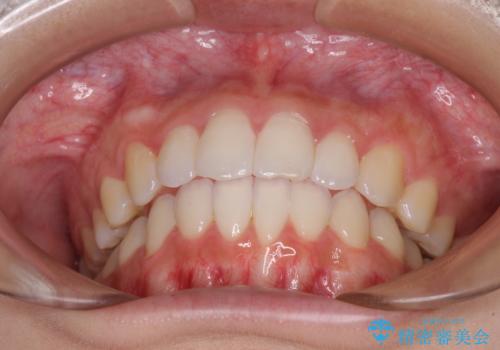

前歯のデコボコと突出感 インビザラインで改善

骨格的な左右差があったため、上下の正中を合わせることは困難かと思われましたが、何とか合わせることができました。

一方、骨格の差は改善できないため、奥歯の咬み合わせに物足りなさを感じました。

奥歯の咬み合わせによる不自由はなく、患者様に大変満足していただきました。